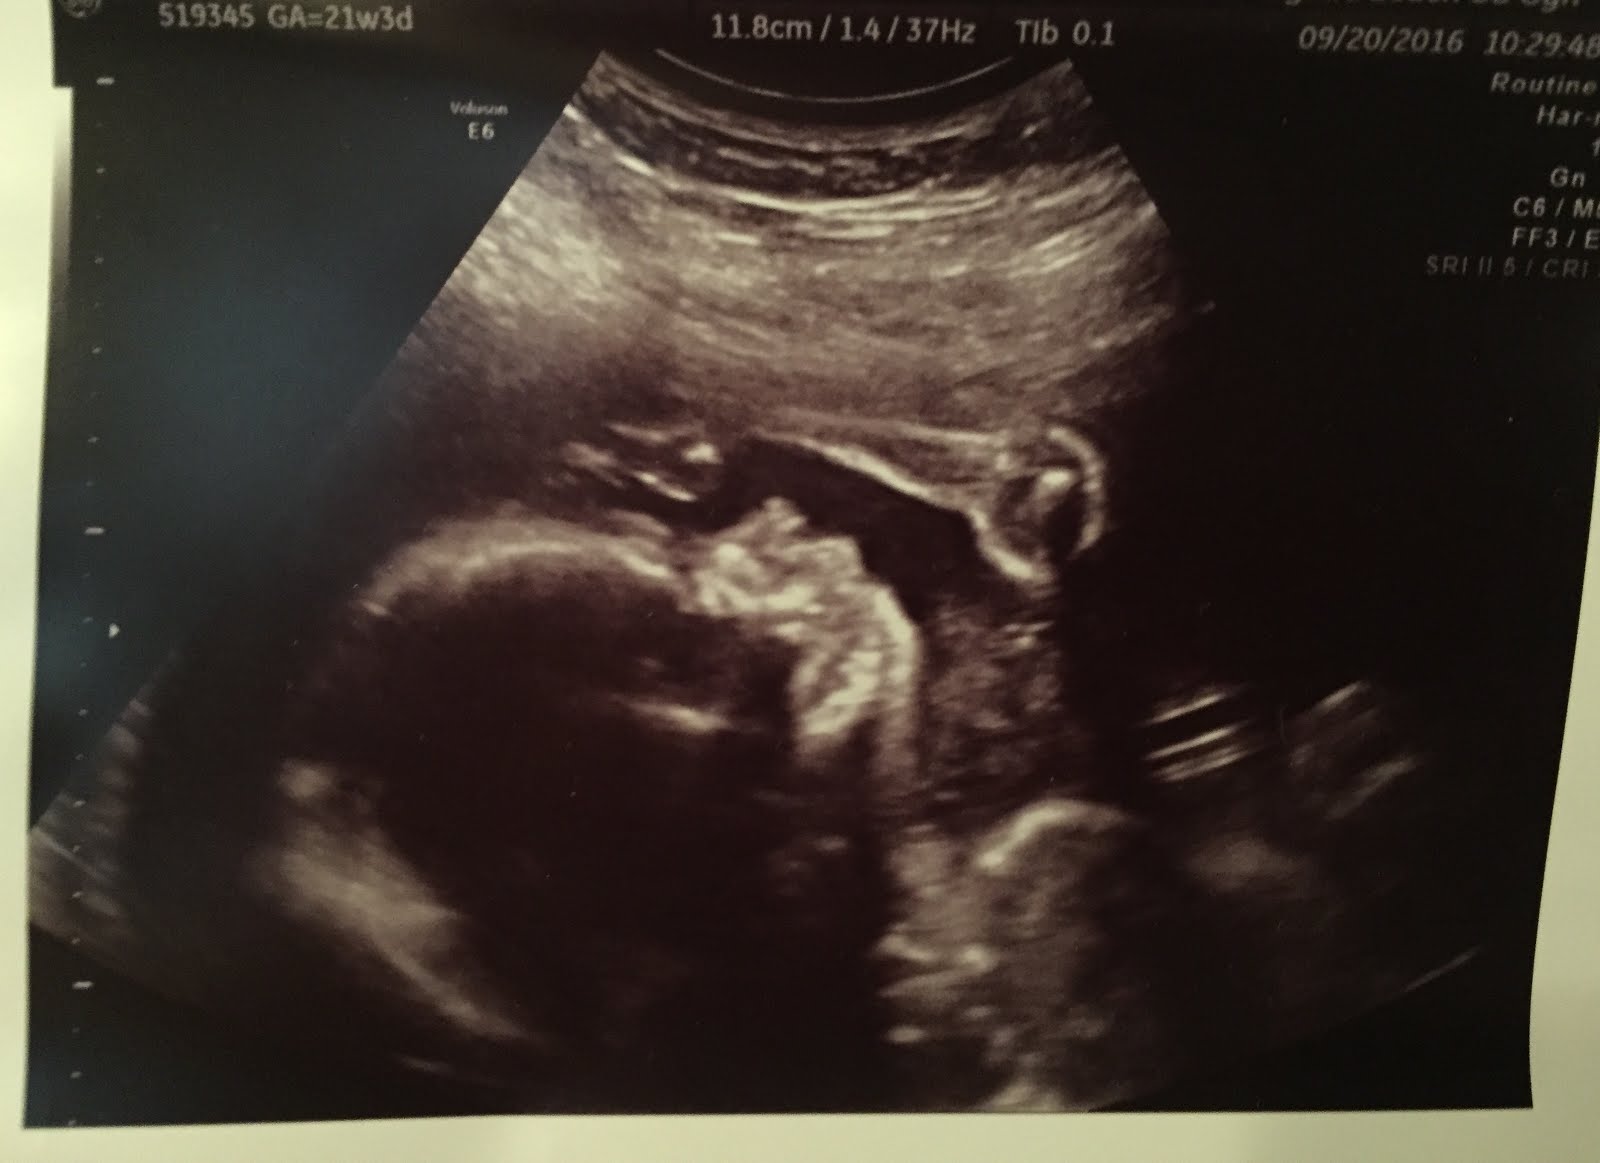

Best Moment this week: Seeing growing baby on the ultrasound!

Baby Movement: Lots of kicks and rolls mostly in my lower stomach and bladder. We saw on the ultrasound that baby is breech with head behind my belly button and feet down so that explains the bladder kicks.

The 20 week ultrasound is my favorite because I love seeing all of the baby's anatomy and confirming that is is healthy and growing. We found out with Reaghan right away during the ultrasound that she was a girl and this time we closed our eyes for the gender pictures. I didn't like having to close my eyes!

Baby was pretty chill during the ultrasound. Didn't really flip and turn much which was different from Reaghan. He/she did keep bring the arms up to the face and even the mouth a lot though. So cute!